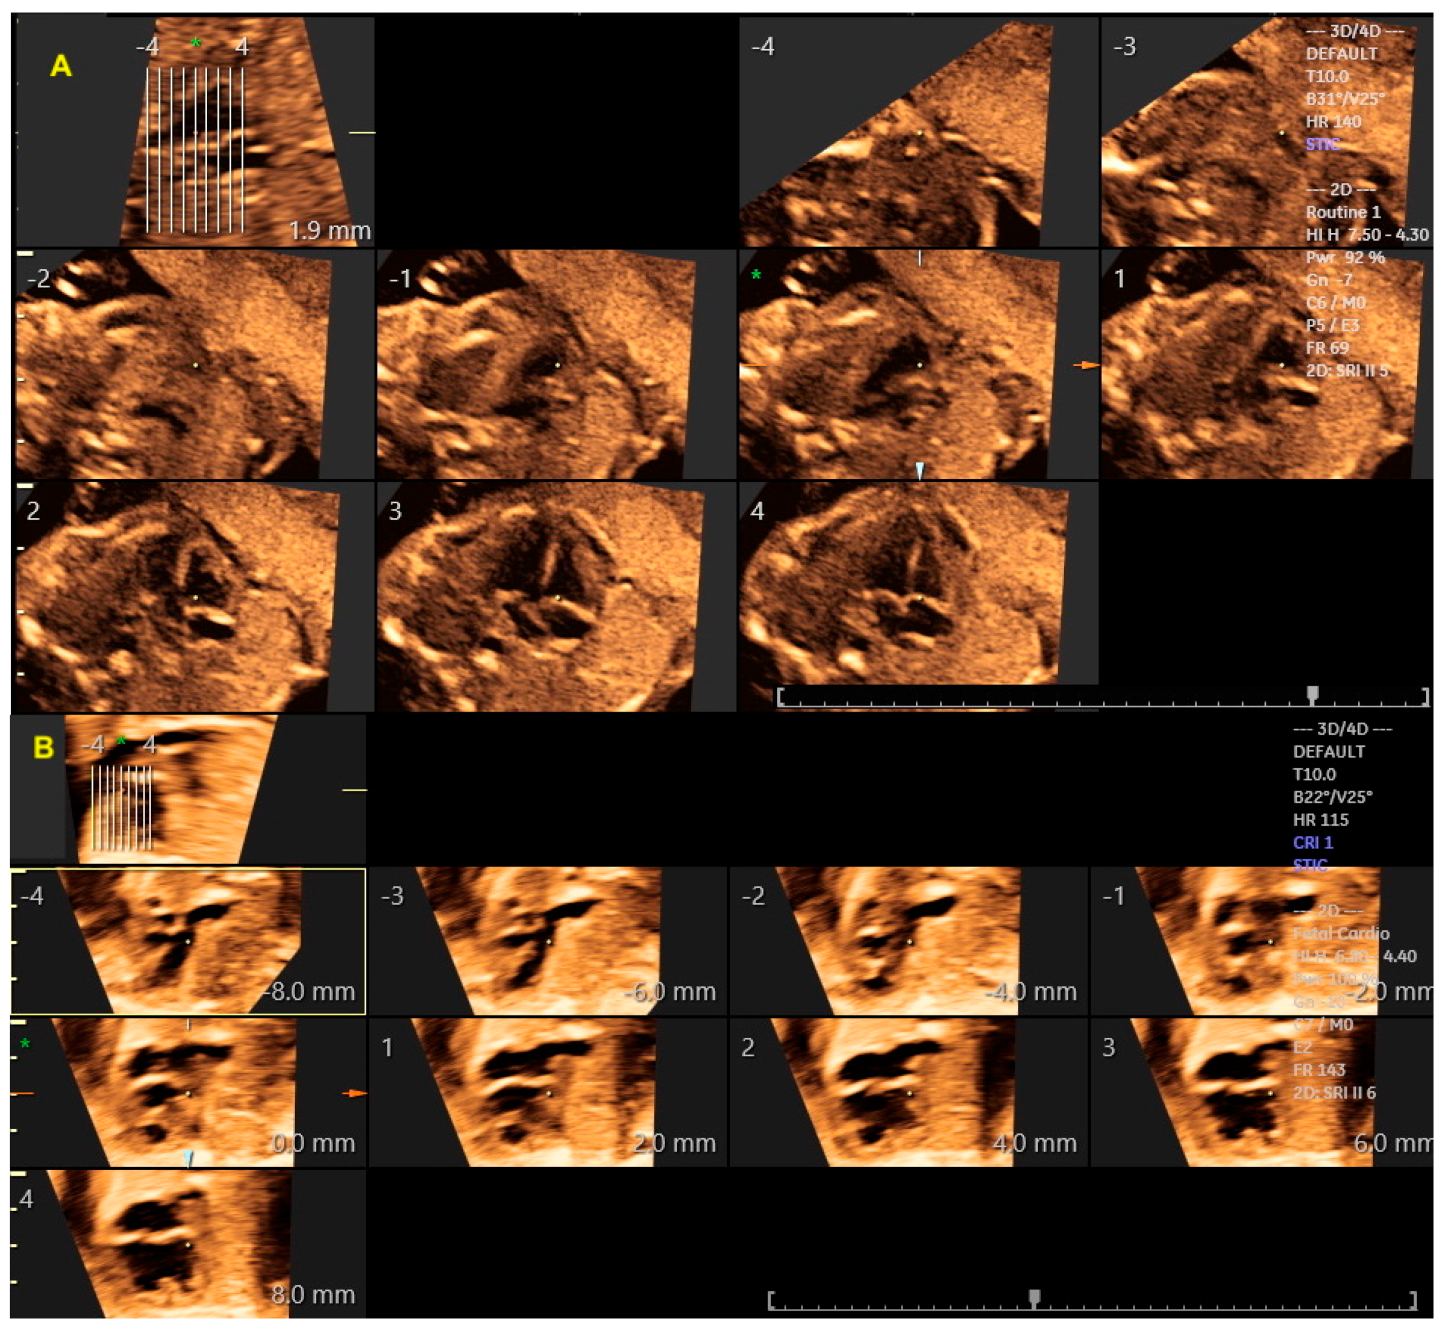

2. Three-Dimensional Ultrasound with Spatiotemporal Image Correlation